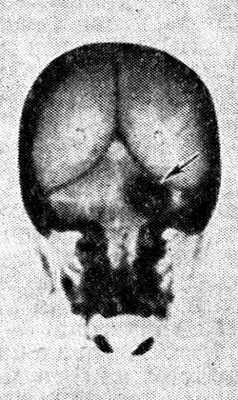

Диагноз патологических процессов, локализующихся в Мостомозжечковом угле, основывается на данных клинической картины и рентгенологических методах исследования — краниографии (см.) и рентгеноконтрастных исследований ликворной и сосудистой систем мозга (см. Вертебральная ангиография).

Рис. 3. Компьютерная томограмма черепа больного с невриномой слухового (преддверно-улиткового) нерва: стрелкой указана тень опухоли в области мостомозжечкового угла.

Тщательное томографическое исследование черепа, в частности пирамид височных костей (см. Томография), применение пневмоэнцефалографии (см.) и цистернографии (см. Энцефалография) позволяют в большинстве случаев выявлять даже относительно небольшие опухоли М. у. Высокой диагностической эффективностью обладает компьютерная томография (см. Томография компьютерная), с помощью к-рой можно обнаруживать объемные образования М. у. диам. до 1,5—2 см (рис. 3).

Краниографическая диагностика опухолей М. у. основывается на местных изменениях в костях черепа, обусловленных непосредственным влиянием опухоли, и отдаленных изменениях, обусловленных смещением мозговых структур и компрессией костей, нарушением оттока цереброспинальной жидкости и смещением ее резервуаров, сдавлением и смещением сосудов в задней черепной ямке.

Рис. 4. Рентгенограммы по Стенверсу височных костей больного с невриномой правого слухового (преддверно-улиткового) нерва: а — виден резко расширенный правый внутренний слуховой проход (указан стрелками); б — нормальная ширина слухового прохода (указан стрелкой) левой (здоровой) височной кости.

Для большей достоверности рентгенол. признаков опухоли производят следующие парные краниограммы больной и здоровой сторон на одной пленке при идентичных условиях съемки: поперечные рентгенограммы височных костей по Стенверсу; прямые рентгенограммы с проекцией пирамид в глазницы; задние полуаксиальные рентгенограммы для выявления деструкции задней поверхности пирамиды. Основное значение имеют снимки по Стенверсу, дающие представление о размерах внутреннего слухового прохода на стороне опухоли, состоянии его верхней и нижней стенок, глубокой ампулярной части, об отношении опухолевого дефекта кости к капсуле улитки и вертикальному полукружному каналу лабиринта (рис. 4, я, б). Иногда более информативны снимки с проекцией пирамид в глазницы.

Рис. 5. Рентгенограмма по Стенверсу черепа больного менингиомой мостомозжечкового угла: стрелками указана тень обызвествленной опухоли.

По данным краниографии иногда можно дифференцировать различные опухоли М. у. Так, менингиомы редко вызывают расширение внутреннего слухового прохода, чаще деструкцию вершины пирамиды и ее поверхностей с неровными очертаниями, нередко наблюдаются известковые включения по периферии опухоли (рис. 5); при холестеатомах наблюдается резкое расширение внутреннего слухового прохода с разрушением передней поверхности пирамиды и линейные дугообразные известковые отметки с гладкими очертаниями узур прилежащих костей.